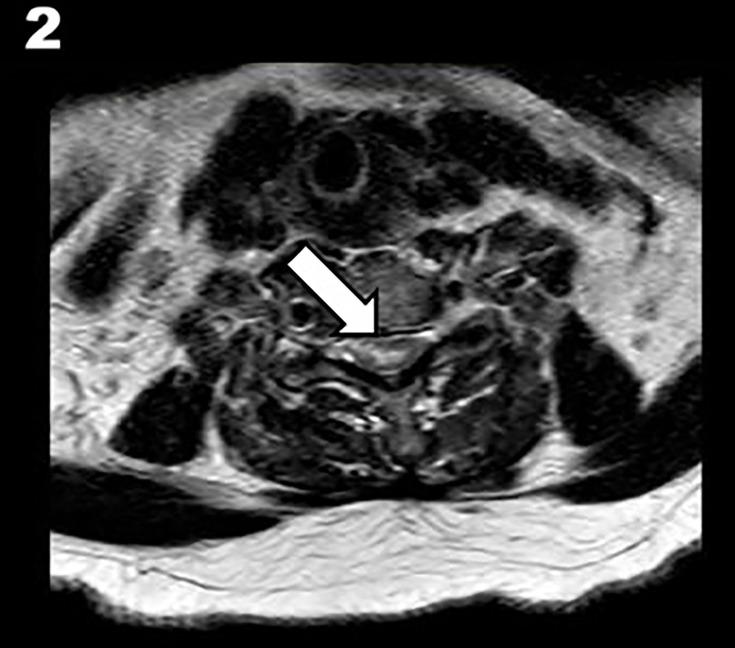

Spinal cord infarction (SCI) is associated with poor clinical outcome. Intravenous thrombolysis (IVT) is a well-established treatment for cerebral ischaemic stroke. However, its efficacy in SCI is unknown.

We present a case of acute spinal cord ischaemia with significant improvement following thrombolysis and review the current literature to explore the safety and feasibility of this treatment.